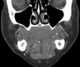

Lingual tonsil

The lingual tonsils are a collection of lymphatic tissue located in the lamina propria of the root of the tongue. This lymphatic tissue consists of the lymphatic nodules rich in cells of the immune system (immunocytes). [Source: Wikipedia ]